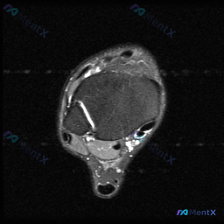

看到这张踝关节MRI,问题问有什么异常,很多人第一反应就是看到软组织积液,但其实背后藏着更关键的问题,我整理一下完整的分析思路给大家。 病例影像基础信息 这是一张踝关节MRI T2序列轴位影像,我们先把所有能看到的征象理清楚: 1. 骨骼结构:影像中心是距骨横截面,皮质骨低信号、骨髓中等信号,骨质轮...

看到这个踝关节MRI的病例,整理了完整的影像资料和分析思路,和大家分享讨论。 病例影像基础信息 这是踝关节MRI T2加权轴位图像,扫描层面为踝关节远端,可见距骨体及周围软组织结构,图像对比度满足观察要求,T2加权像液体呈高信号。 核心影像发现 1. 骨结构:距骨及周围骨性结构骨髓无异常高信号,骨皮...

刚看到这份踝关节MRI读片需求,整理了完整的观察和分析思路分享给大家。 病例基本影像信息 本次读片基于踝关节MRI-T2序列轴位图像,扫描层面为踝关节远端轴位,可清晰辨认胫骨、腓骨、距骨以及后方跟腱等正常解剖结构。T2序列对液体和水肿敏感,正常肌腱韧带应为低信号(黑色),液体/水肿为高信号(白色)。...